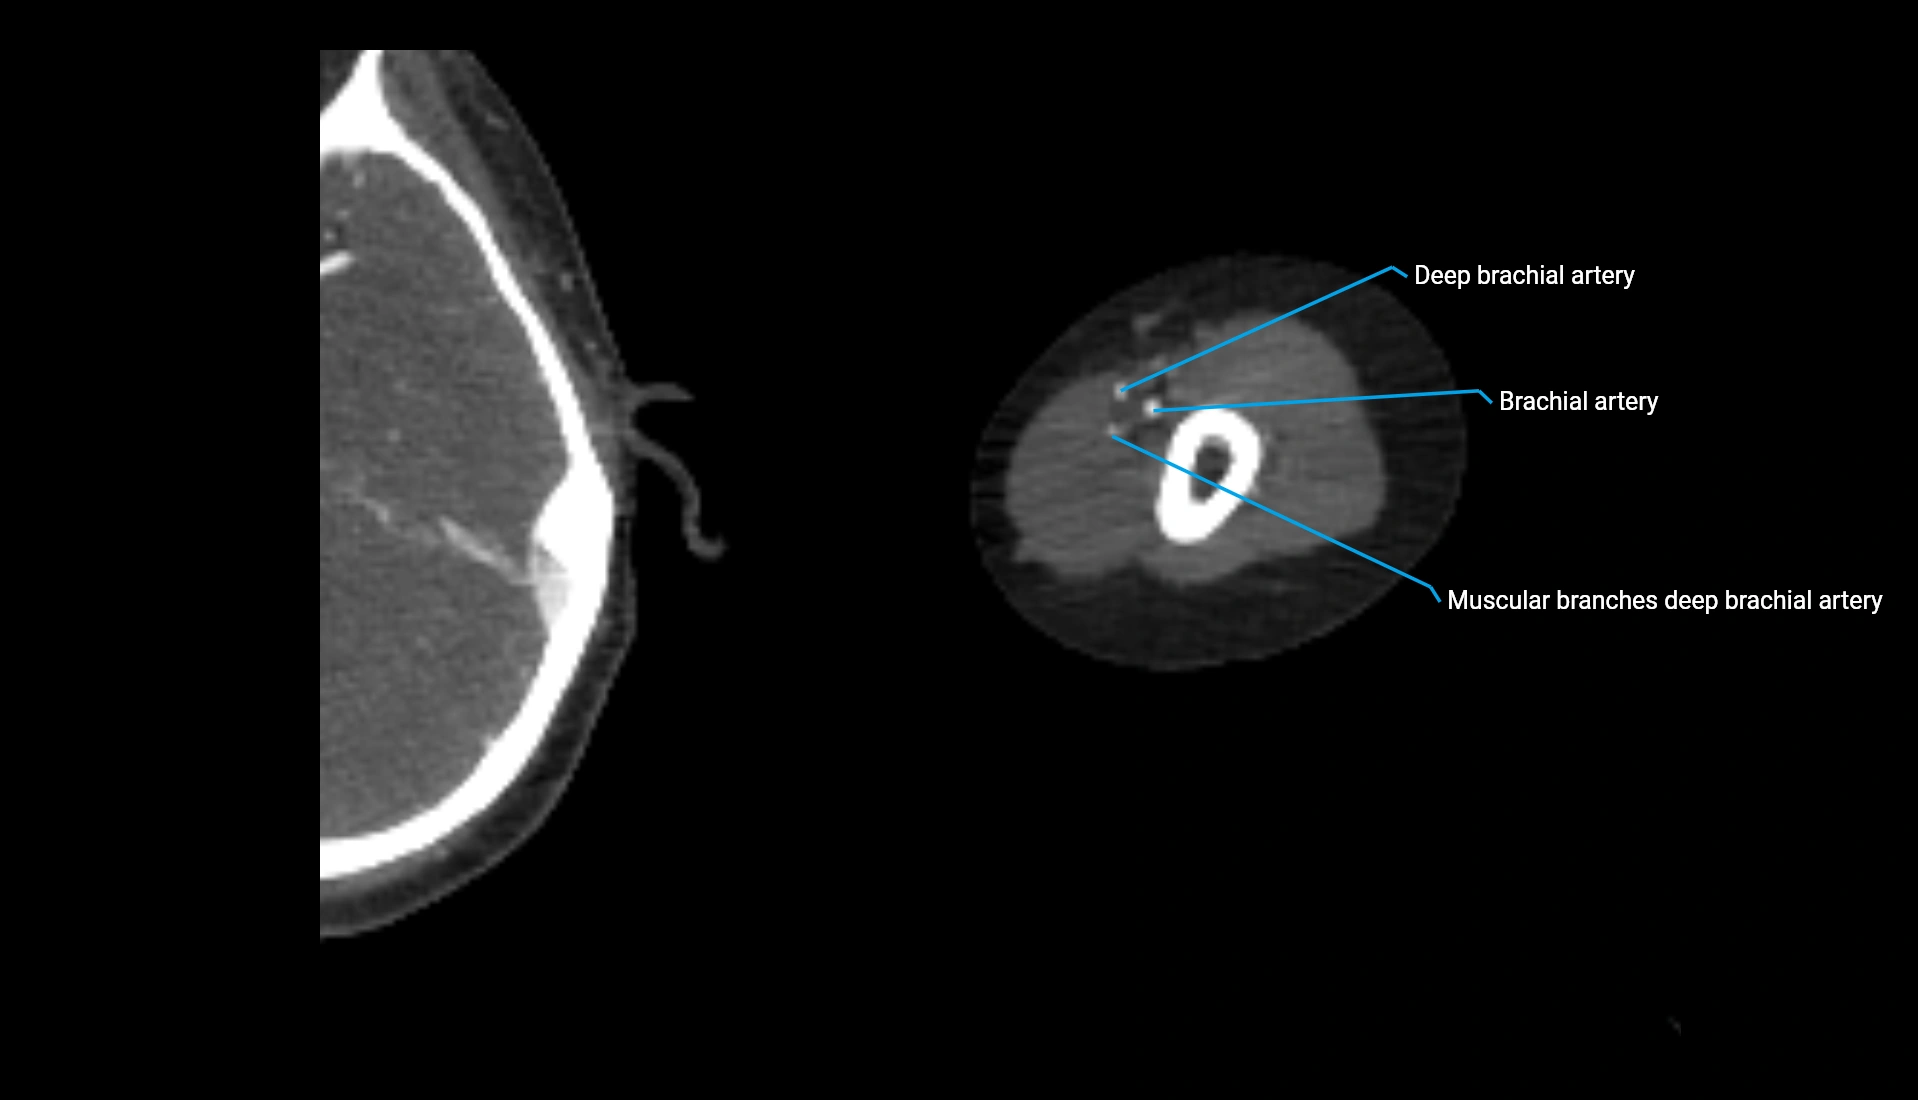

CT Appearance

Non-Contrast CT:

• Cortex: High-density, sharply defined

• Subchondral bone: Dense cancellous matrix

• Articular surface: Smooth concave contour articulating with the capitellum

• Excellent for evaluating bone integrity, alignment, and subtle fractures